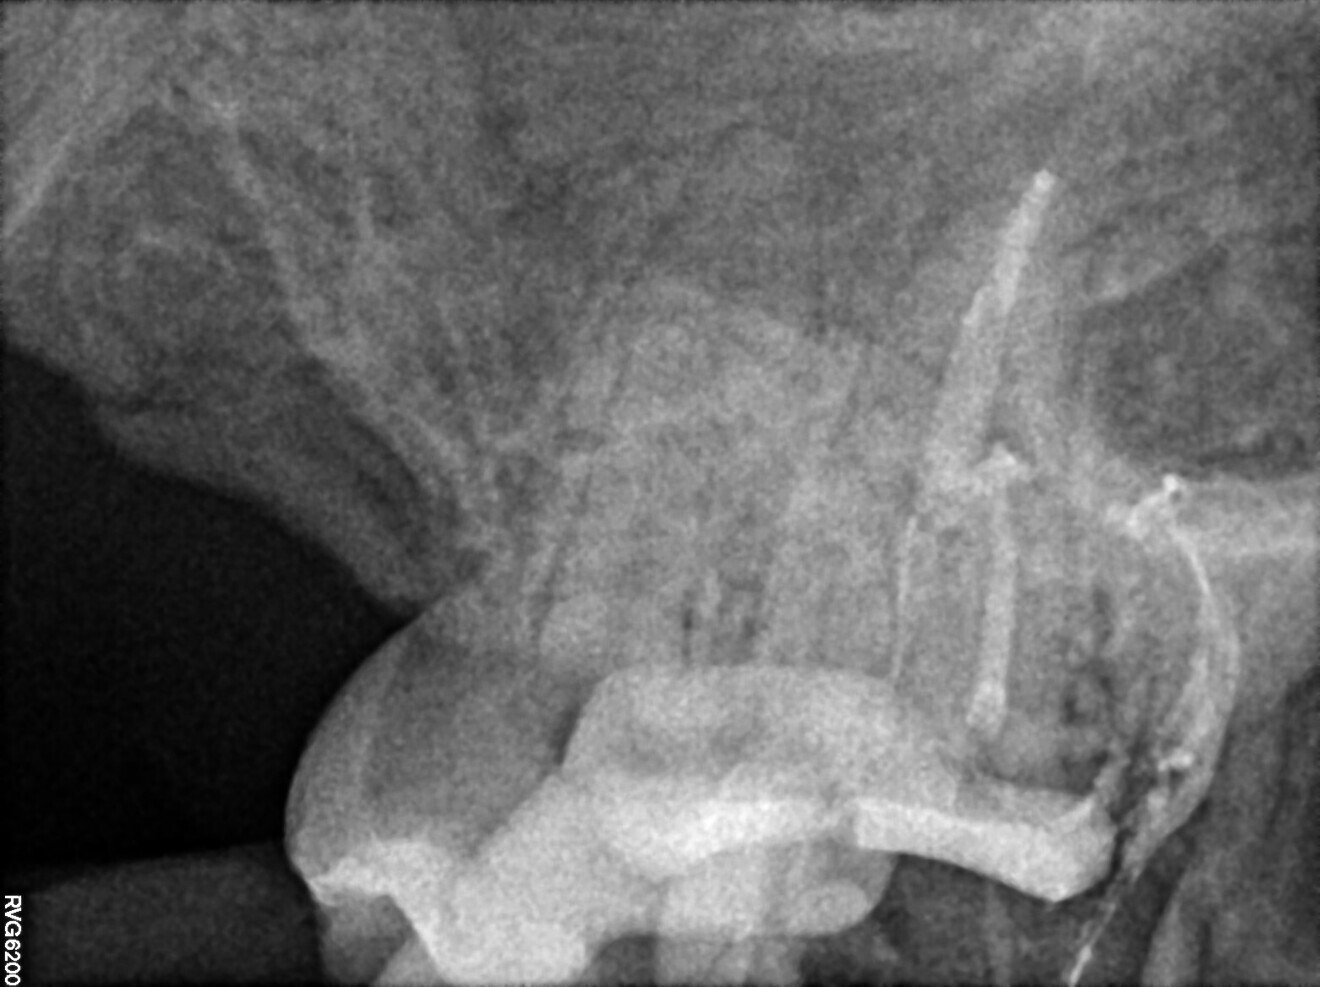

A 49-year-old patient was referred to Dr Witkowiski’s dental office for endodontic retreatment owing to a major problem with canal instrumentation and problems with location of the canal space in the distal aspect. Radiographic examination was performed (Fig. 36).

After removing the temporary restoration and lowering the walls of the cavity because of the biomechanics, it was attempted to reach the apical zone. Unfortunately, it was impossible to achieve patency in the distal root. For this reason, the use of laser-assisted endodontics was decided on.

After initial preparation of all accessible spaces with the R25 RECIPROC blue instrument (VDW) in the distal root until the file met with resistance, the irrigation protocol with laser assistance was followed. The mesial canals were prepared conventionally up to the apical zone to size 25/0.04 with VDW.ROTATE files (VDW).

After preparation of all accessible spaces, the final irrigation protocol with continuous irrigation with 5.25% sodium hypochlorite and continuous activation was performed using the Er,Cr:YSGG laser with the RFPT5-14 tip (Figs. 37 & 38). After the cleaning stage of the irrigation protocol (part of the “safe endo concept”), the root canal system was examined for any remaining debris (Figs. 39 & 40).

During this treatment, owing to the impossibility of mechanically instrumenting the apical area in the distal root, it was decided to make use of the cavit piston technique of obturation using VDW.1Seal (Figs. 41–43). After obturation (Fig. 44), radiographic examination was performed in order to confirm proper irrigation and proper 3D obturation of the root canal system (Figs. 45 & 46).